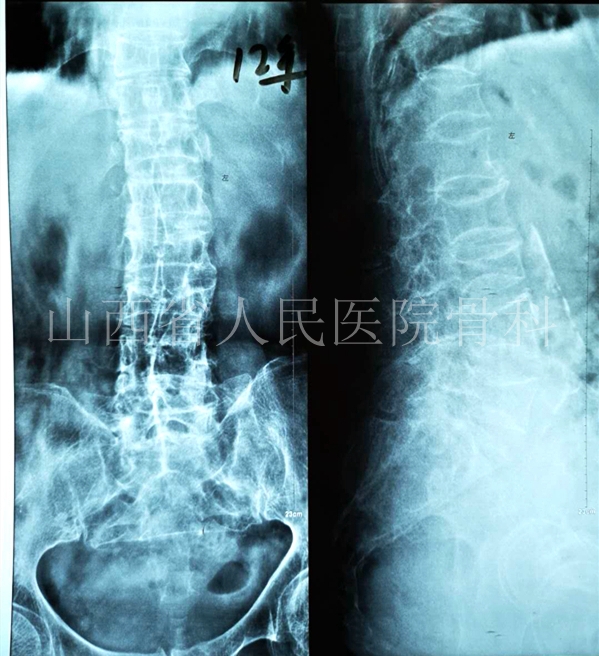

好景不长2013年7月再次因腰背疼痛住院治疗,此时背痛难忍的患者选择了PKP治疗。

2013年7月再次因腰背疼痛加剧检查发现T12、L2、L3、L5压缩骨折+T8、T11新发压缩骨折、骨密度结果显示重度骨质疏松

2013年7月对新发的T8、T11椎体行PKP治疗